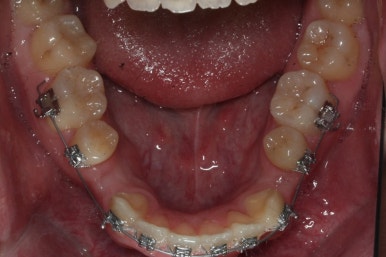

윗니는 아직 가지런하게 하는 작업 중이며, 아랫니는 가지런하게 하는 작업은 거의 다 되었습니다.

이제 아랫니는 이 뽑은 자리를 앞뒤로 당겨서 없애주어야 합니다. 보통은 앞니가 뒤로 많이 들어오기 때문에 이번 환자분 처럼 앞니가 거꾸로 물리는 경우 앞니를 제대로 물리게 해줄 수 있습니다.

계속 윗니는 가지런히 해주고 있으며 아랫니는 앞뒤를 뒤로 당기고 있습니다.

거꾸로 물리던 앞니가 서서히 개선되어 가는 것을 볼 수 있습니다.